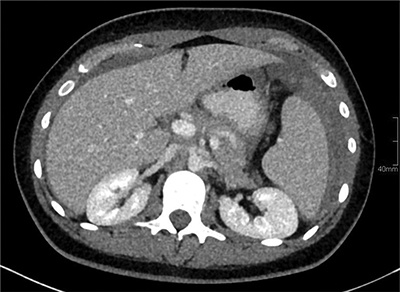

Figure 2

Contrast-enhanced abdominal CT shows a haemoperitoneum. A hyperdense, perisplenic collection with layering suggests an acute perisplenic haematoma.